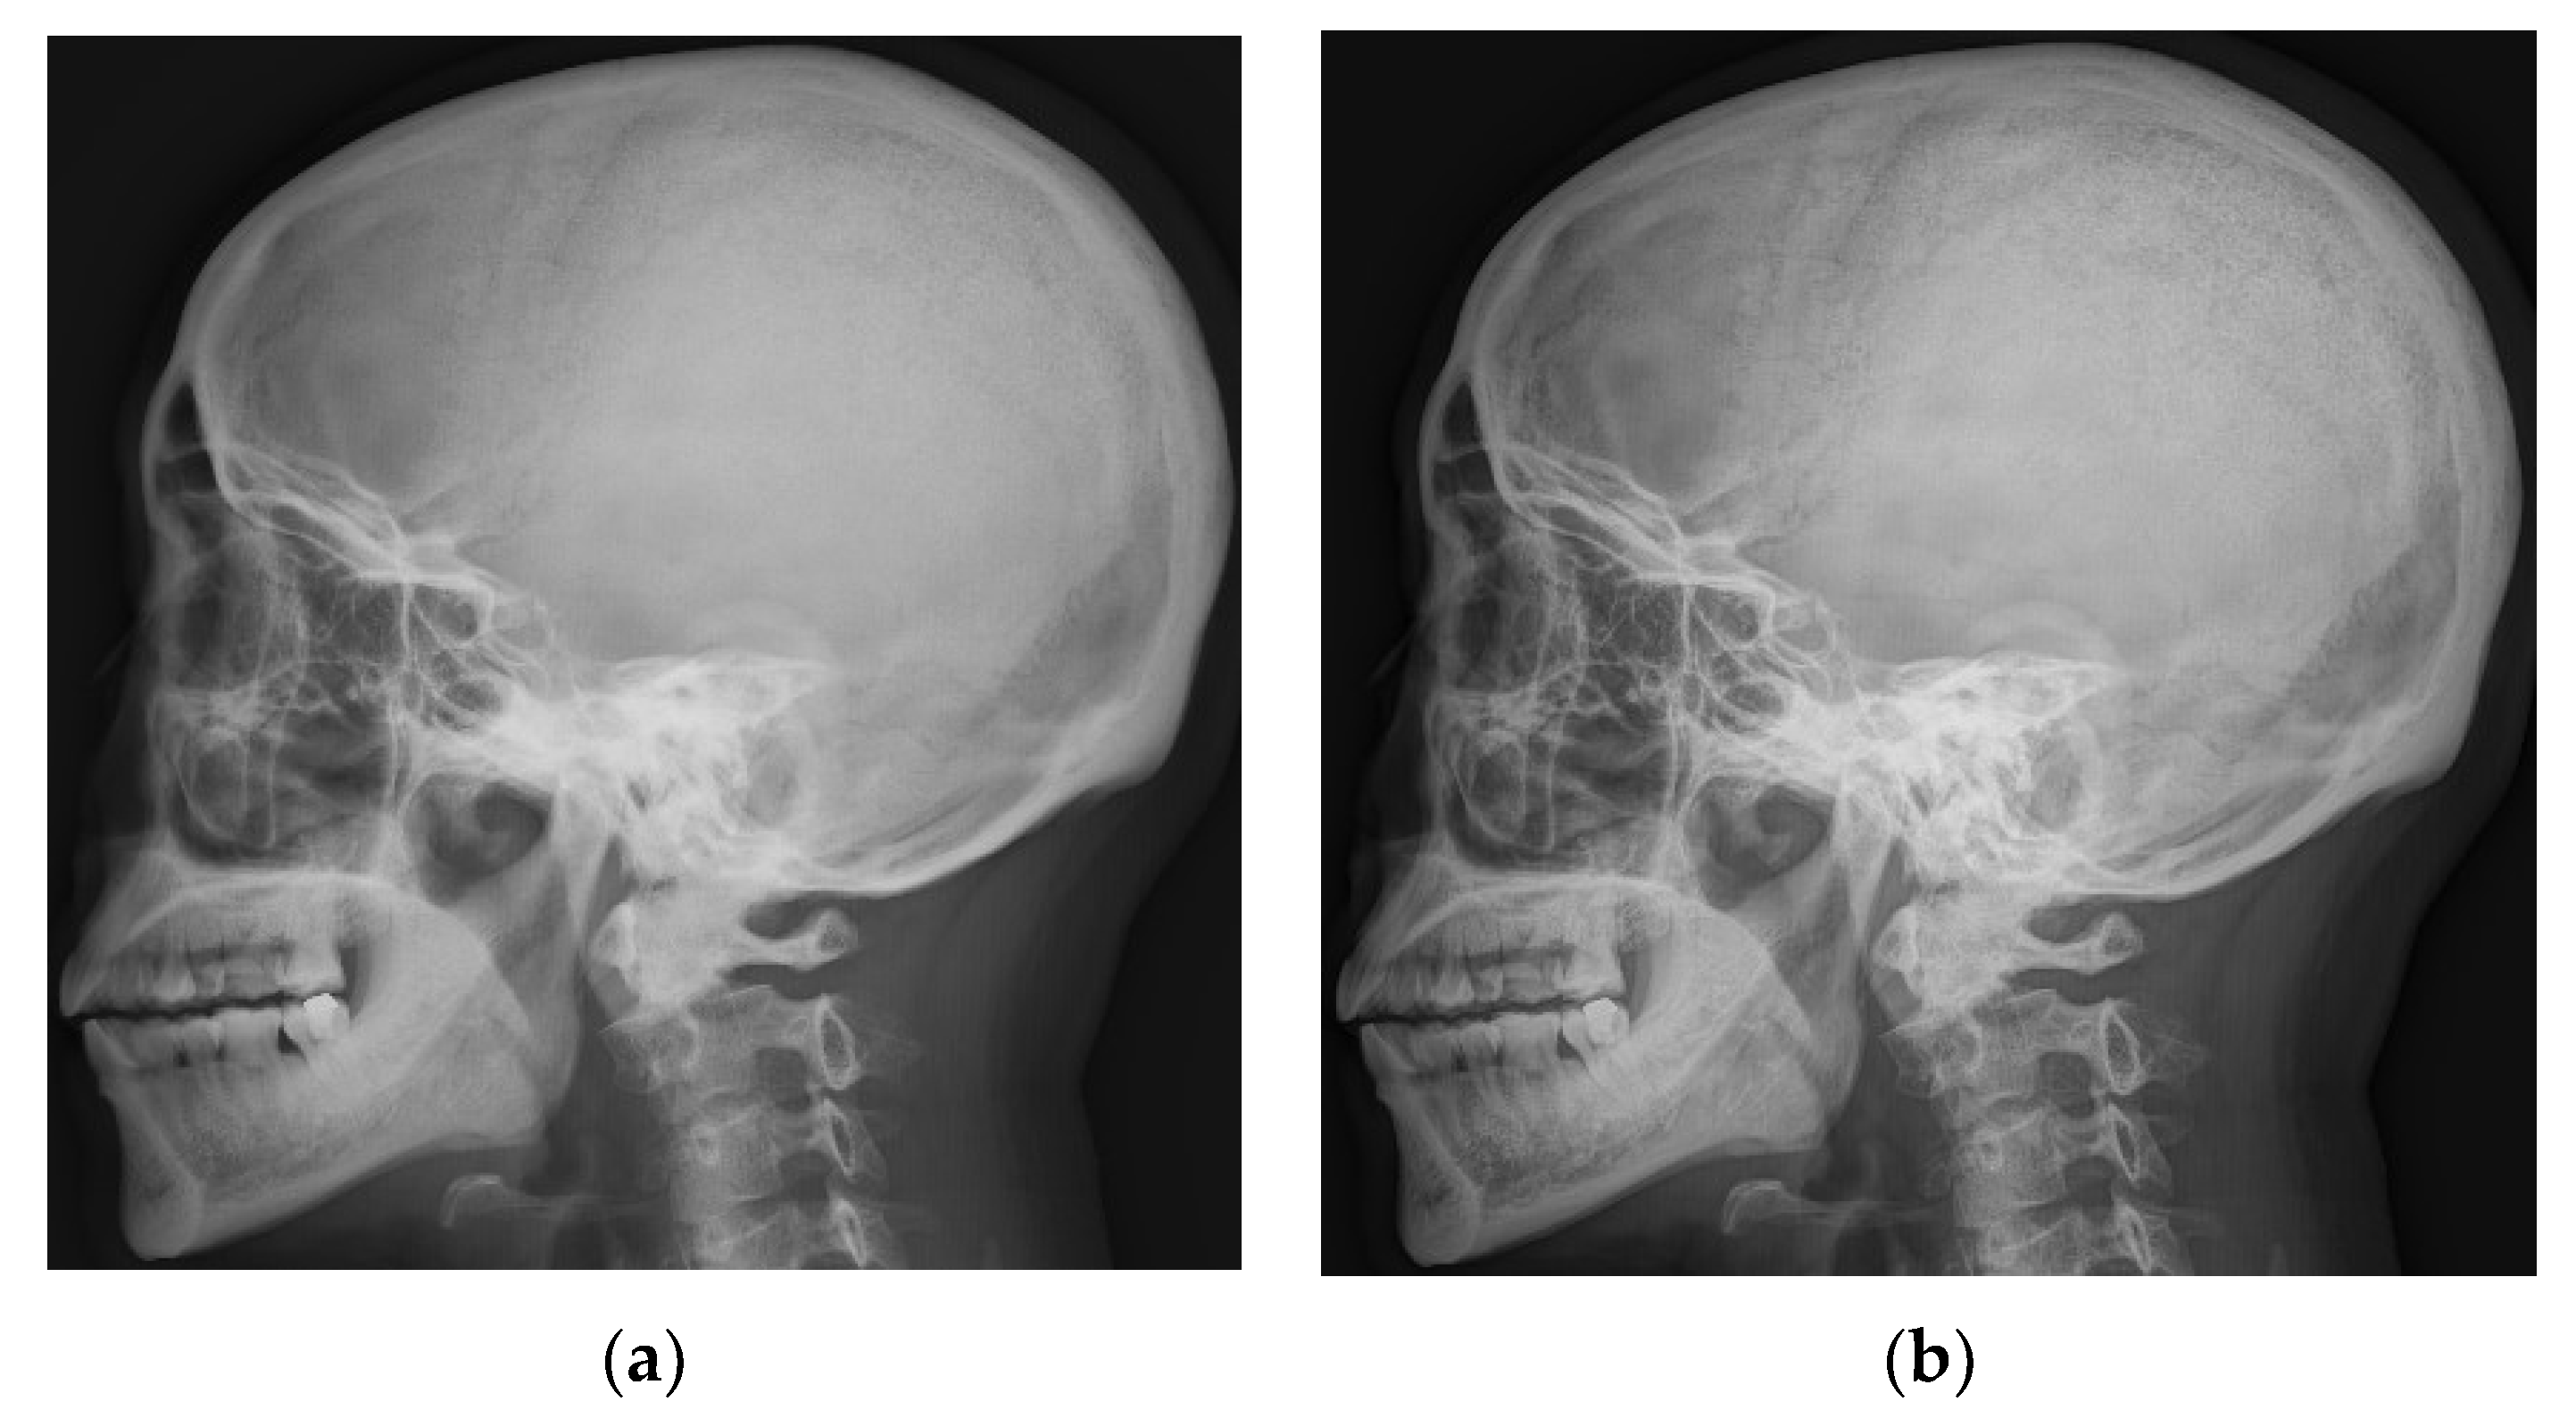

4.1. Simulations for Multicale Diagnostic Detail Enhancement on DR Images